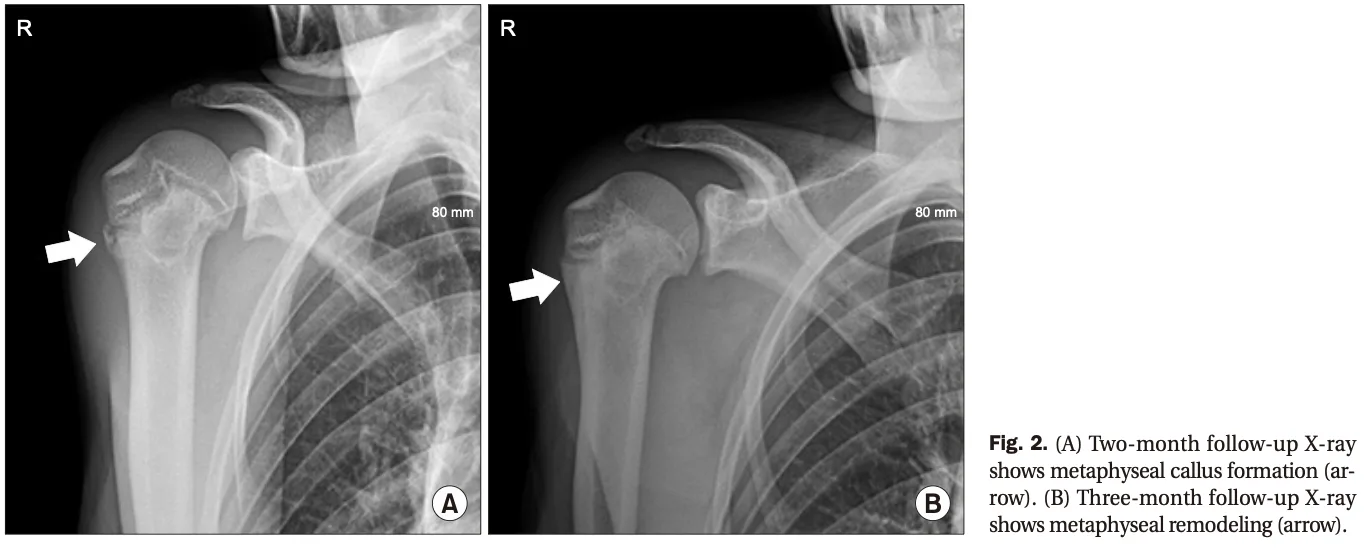

これは, 上腕骨の近位骨端線損傷に対する修復過程で認められます.

3ヶ月後のX線写真(B)では, 新しく作られた骨が成熟して, 普通の骨に変化しています.

引用元:Park JY. Little league shoulder: case reports. Arthrosc Orthop Sports Med. 2020. 7.